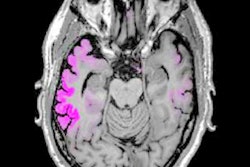

Flortaucipir-PET scans revealed high amounts of tau protein in brain regions associated with chronic traumatic encephalopathy (CTE) in former professional football players, potentially enabling this disease to one day be diagnosed before death, according to new research in the New England Journal of Medicine.

The researchers used automated image-analysis algorithms to compare the differences in mean standardized uptake volume ratios (SUVRs). Significantly greater overall uptake of flortaucipir -- and, therefore, tau protein -- was evident among the former football players, compared with controls. The most significant differences were in the bilateral superior frontal, bilateral medial temporal, and left parietal regions, all of which are associated with confirmed post-mortem cases of CTE.